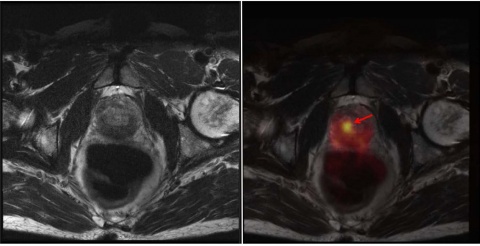

In der Abteilung Nuklearmedizin des BwZKrhs Koblenz wurden seit Juli 2015 insgesamt 193 Untersuchungen mit der PSMA PET/CT durchgeführt. Wir hatten die Gelegenheit in einer ersten Serie von Patienten nach Etablierung der PET/MRT im BwZKrhs Koblenz 34 Patienten, die eine PET/CT erhalten hatten, unmittelbar im Anschluss an diese einer PET/MRT-Untersuchung zuführen zu können (Abbildung 3).

Bei dieser (zunächst noch kleinen) Gruppe von Patienten fanden sich in 31 Fällen (31/34) Übereinstimmungen der Befunde. Keine einzige zusätzliche pathologische Veränderung (Läsion/Lymphknoten/Lokalrezidivsituation) wurde erst durch die zweite Untersuchung erkannt.

In drei Fällen (3/34) konnte eine Diskrepanz aufgezeigt werden; bei zwei Fällen war das PET/CT, in einem Fall das PET/MRT überlegen.

Bei einem Patienten waren drei im PET/CT hochstoffwechsel-aktive Prostatakarzinomherde im PET/MRT nicht abgrenzbar; der intraprostatische PET/MRT-Befund war nicht beurteilbar.